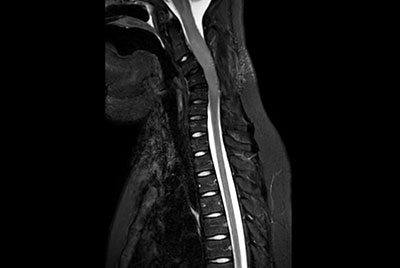

Pediatric Total Spine with spina bifida